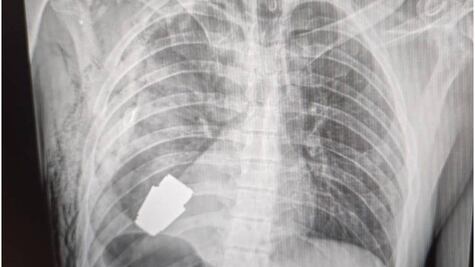

Los cirujanos llevaron a cabo una delicada operación neutralizando el explosivo que estaba alojado justo debajo del corazón del soldado, según informó el gobierno de Kyiv